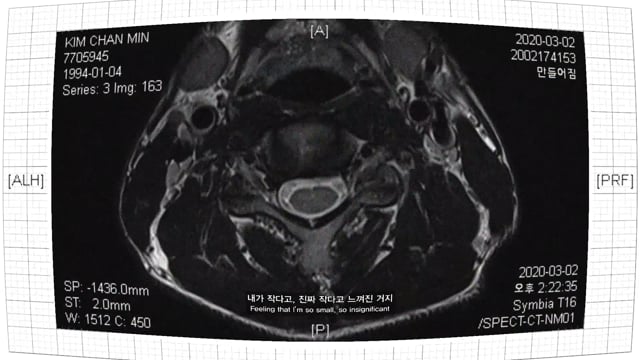

During MRI scanning, I would fall into a profound deception, and in this unpredictable space, all alone and completely disconnected from the outside world, I would travel the universe and ponder about incidents that I would never be able to experience. Incomprehensible yet significant senses and experience that I accidentally faced one day. And the goosebumps from the realness of those moments is weighing down on me. Based on such experience, I visualized my fictious stories along with those of others.